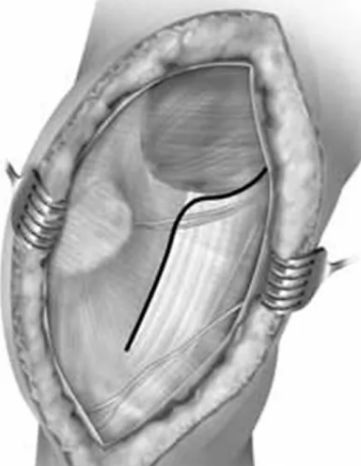

Gerdy结节截骨入路

入路同胫骨平台骨折的Gerdy结节截骨入路(如下示意图) 。平行于胫骨纵轴截取Gerdy结节骨块(大约1cm宽*2cm长*1cm厚)。然后将骨块连同其上附着的髂胫束向上翻转后能完全显露整个股骨外髁。

适用于Letenneur I、II、III型外髁Hoffa骨折,特别适合II型及外髁后部粉碎者。

该入路对外髁后部的显露较充分,可直视下由后向前打螺钉或完成支持钢板的固定。外髁Hoffa骨折固定完成后,再以带垫片的螺钉通过预先钻孔将Gerdy结节原位钉回(截骨前预钻孔!)。